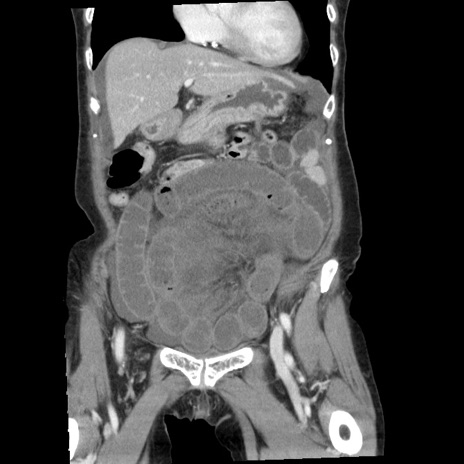

症例1(冠状断像)

【症例】80歳代女性

【主訴】腹痛

【現病歴】8時間前から腹痛あり来院。

【既往歴】糖尿病、脂質異常症、子宮体癌にて子宮全摘術

【身体所見】意識清明・会話良好だが腹痛で苦悶様、全腹部にわたって反跳痛と圧痛あり

【データ】WBC 13600、CRP 0.14、LDH 224、CK 90